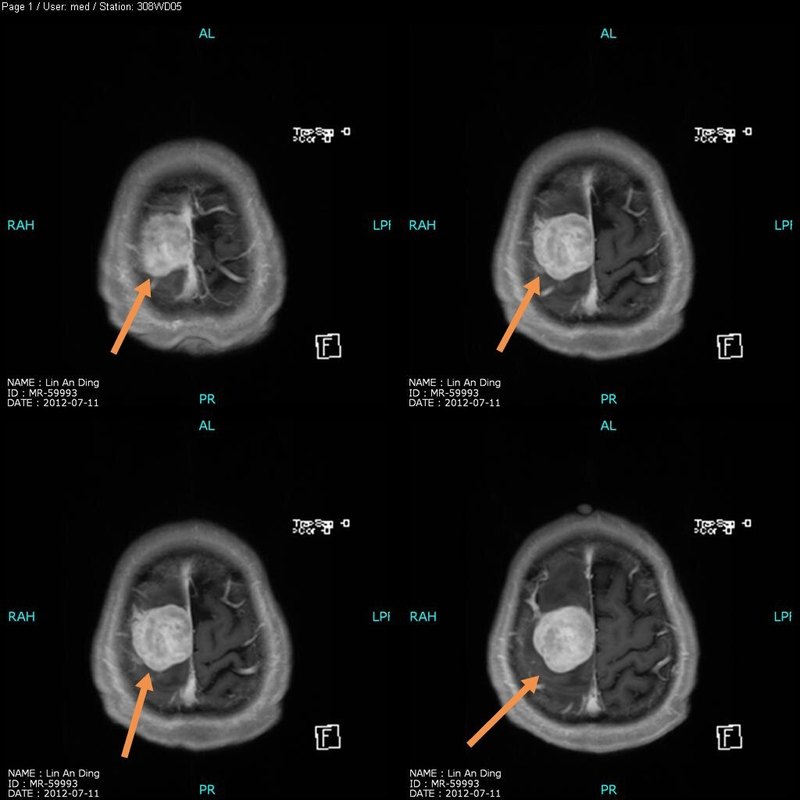

患者女性,41歲,因反復(fù)頭暈頭痛、走路不穩(wěn)半月來診。體檢:小腦性共濟失調(diào)。 顱腦核磁共振檢查結(jié)果:第四腦室腫瘤。 檢查結(jié)果如下圖: 治療:手術(shù)在全麻下進行,后正中入路,顯微鏡下完全切除腫瘤,手術(shù)順利,手術(shù)后病人神志清除,術(shù)后第一天復(fù)查核磁共振,術(shù)后十四天康復(fù)出院,無后遺癥,病理檢查結(jié)果為室管膜瘤(II級)。 術(shù)后復(fù)查核磁共振如下圖: 點評:本病例腫瘤來源于四腦室底,與腦干關(guān)系密切,術(shù)中在顯微鏡高倍鏡下把腫瘤從腦干分離,手術(shù)難度、風(fēng)險大,容易損傷腦干導(dǎo)致昏迷不醒,本手術(shù)成功完全切除腫瘤,不留后遺癥。